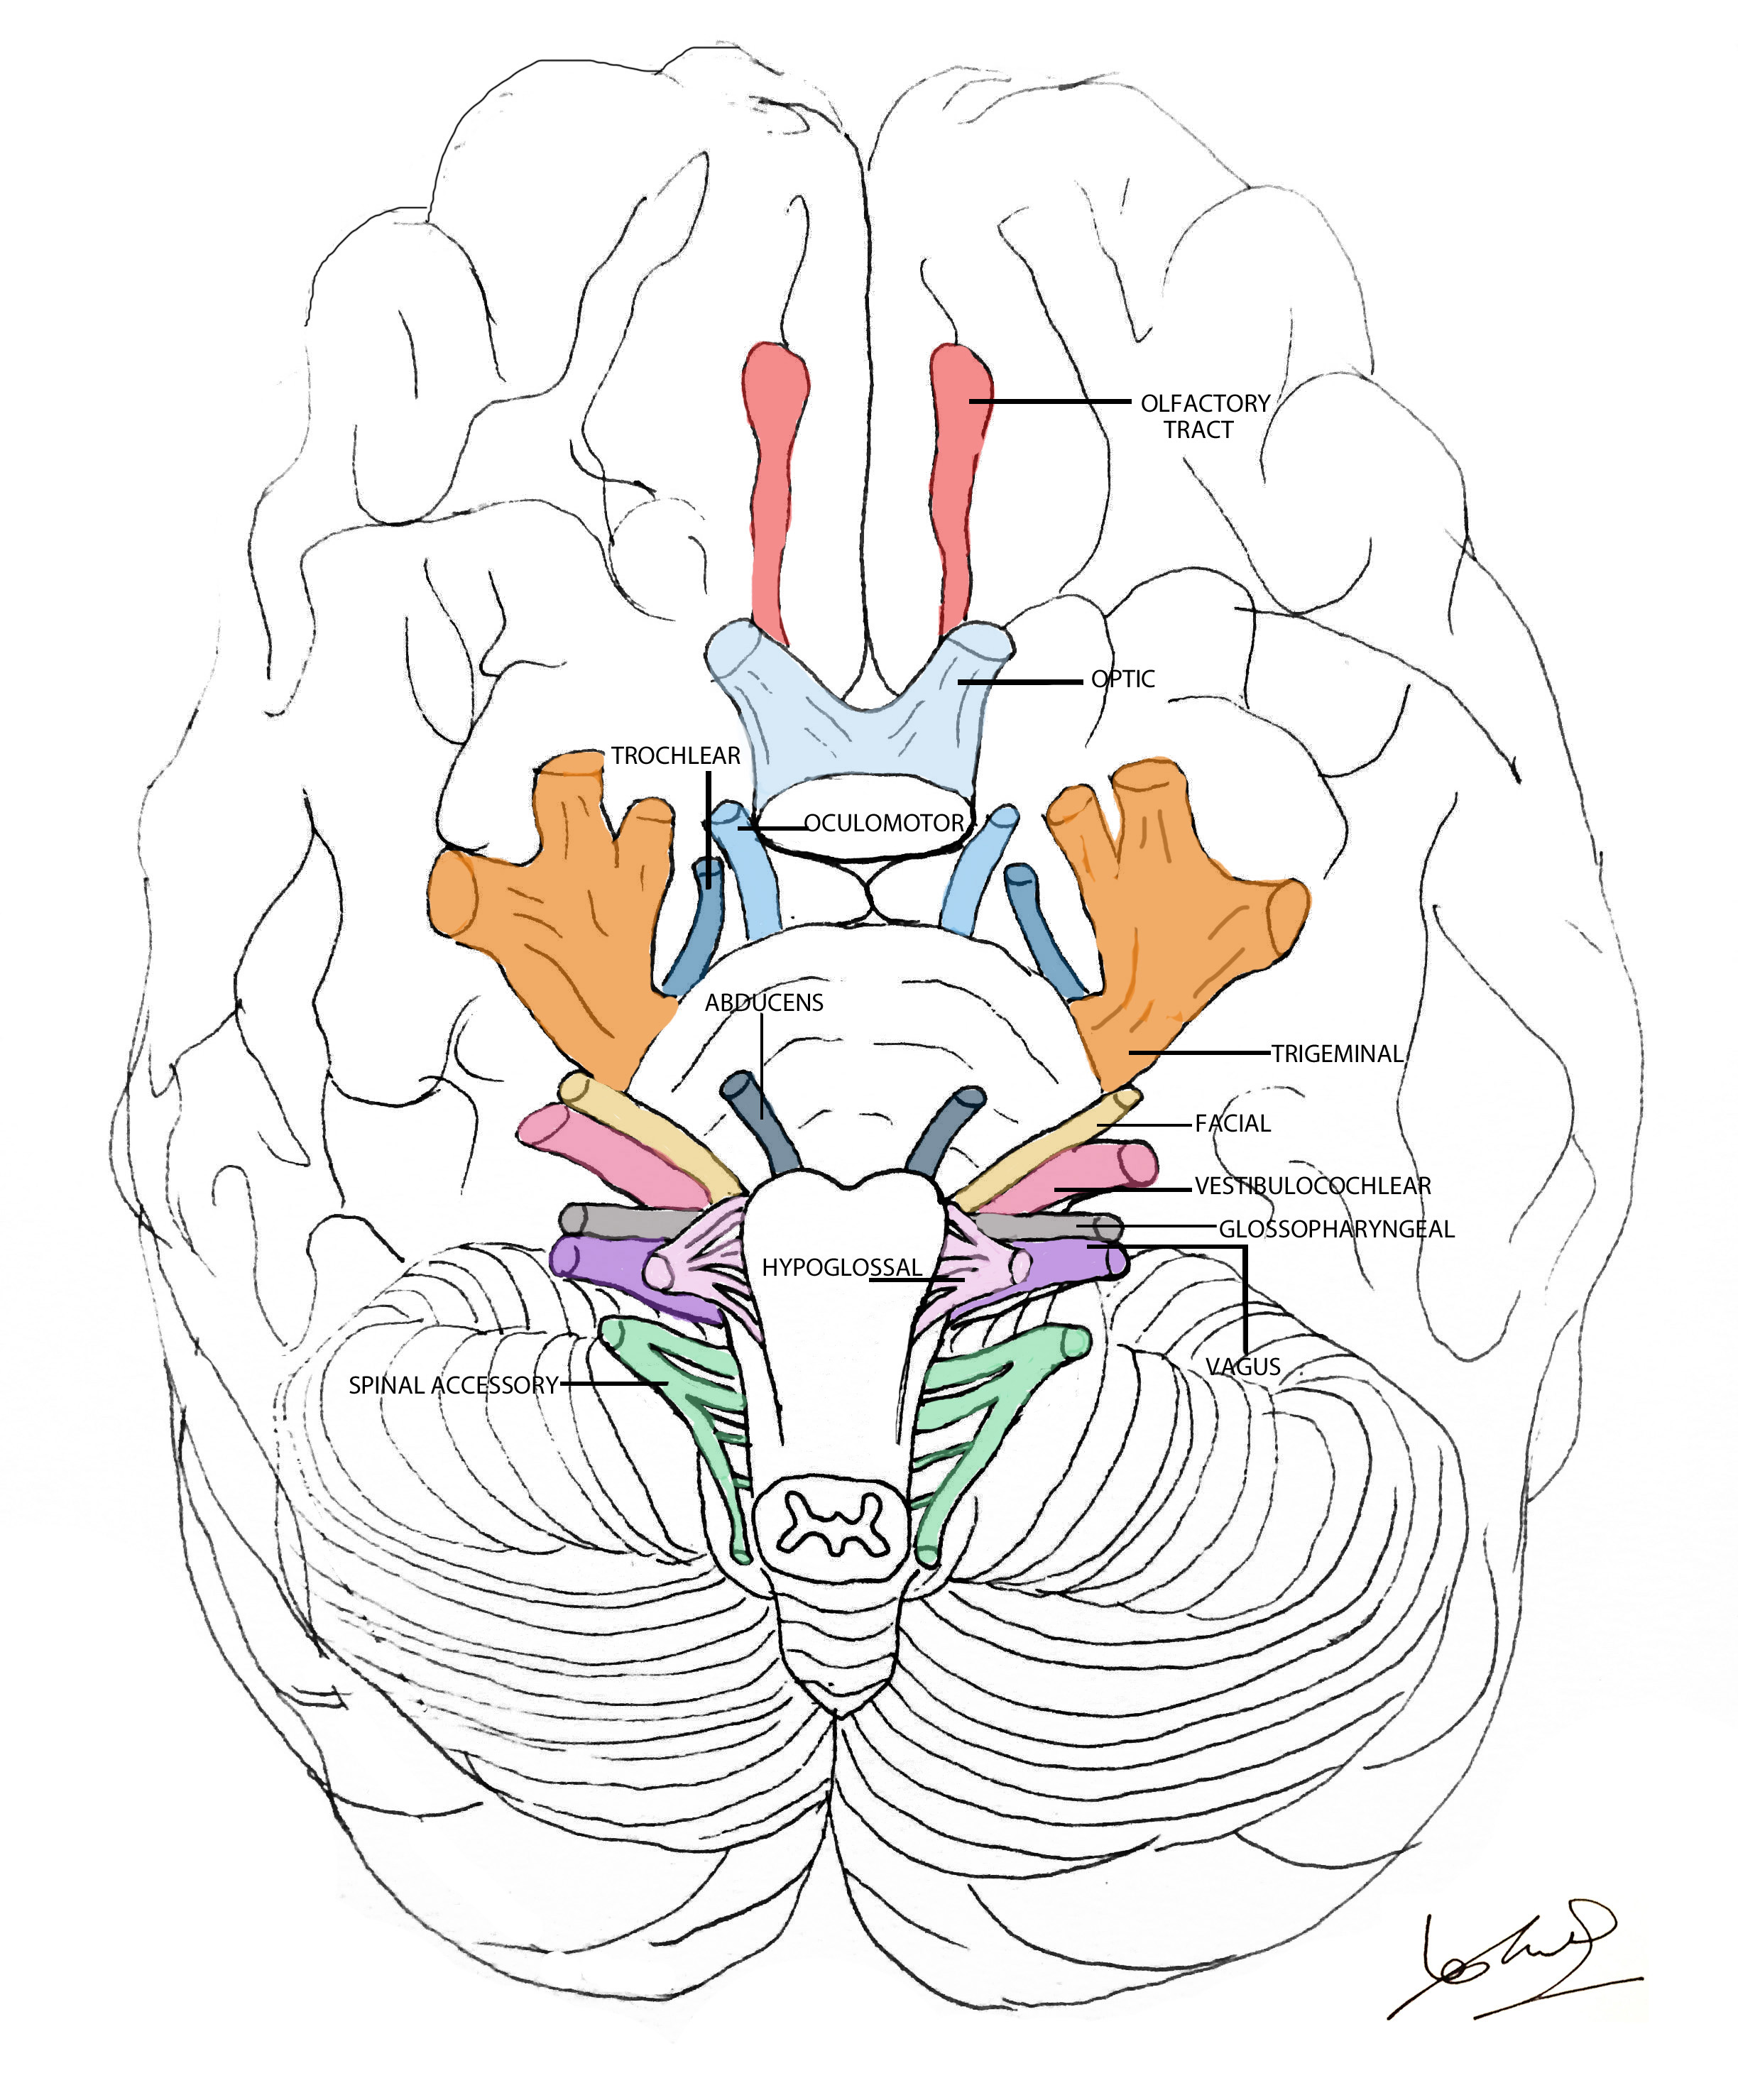

Motor Cranial Nerves – Anatomy, Functions & Components | Kenhub

Motor cranial nerves: Anatomy, functions and components | Kenhub

Why Should You Perform a Cranial Nerve Exam? | Cranial nerves, Medical …

You’ve Got Some More Nerve(s): The Cranial Nerves

Cranial Nerves – Anatomy and Functions | GetBodySmart

Cranial nerves explained | Geeky Medics